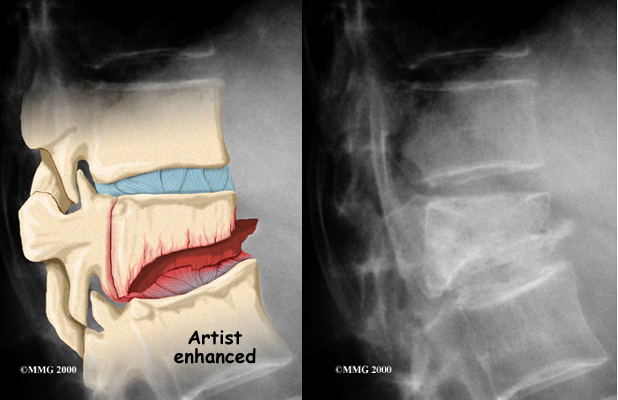

If your doctor believes there is a compression fracture, are ordered. X-rays can show fractures of the vertebrae.

If your doctor believes there is a compression fracture, are ordered. X-rays can show fractures of the vertebrae.

When an X-ray confirms a compression fracture, computed tomography (a CT scan) may be ordered. This is a detailed X-ray that lets the doctor see slices of the body's tissue. The image can show whether the compression fracture has caused the area to become unstable from the injury.

If symptoms suggest problems with the spinal cord, the doctor may combine the CT scan with myelography. To do this, a special dye is injected into the space around the spinal canal (the subarachnoid space). When the CT scan is performed, the dye highlights the spinal cord and spinal nerves. The dye can improve the accuracy of a standard CT scan for diagnosing the health of the spinal cord and spinal nerves.

Magnetic resonance imaging (MRI) can show the doctor problems affecting the nerves or causing pain. The MRI machine uses magnetic waves rather than X-rays to show the soft tissues of the body. It shows problems in other soft tissues such as the discs and spinal cord. This machine creates pictures that look like slices of the area your doctor is interested in. The test does not require special dye or a needle.